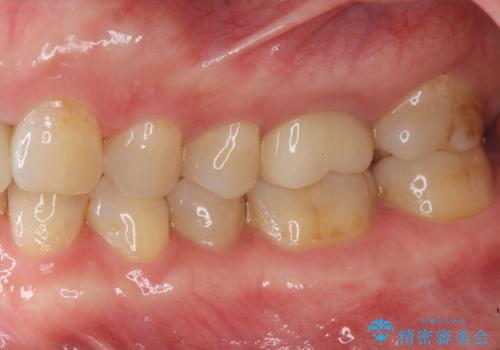

治療後、明るくなった口腔内を見て大変満足いただくことができました。

色調だけでなく、精密な治療を行うことで虫歯の再発の確率を下げることも可能になります。